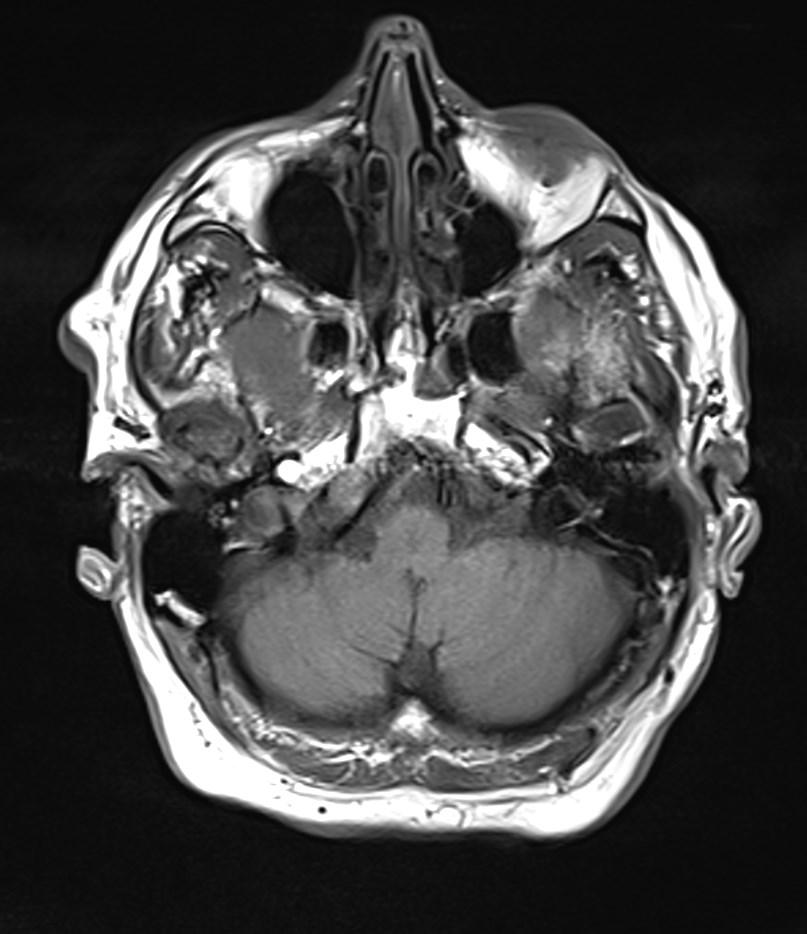

Loss of the signal void was detected on the right vertebral artery on the axial T2 weighted image (arrows).